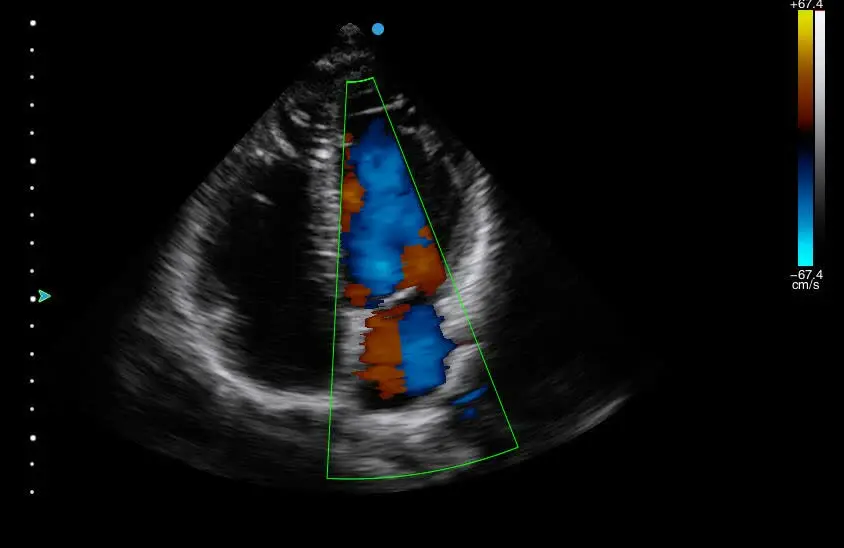

SY-A2300 Cardiac Diagnosis Portable Ultrasound Scanner, Excellent Image 3D 4D Echo Machine